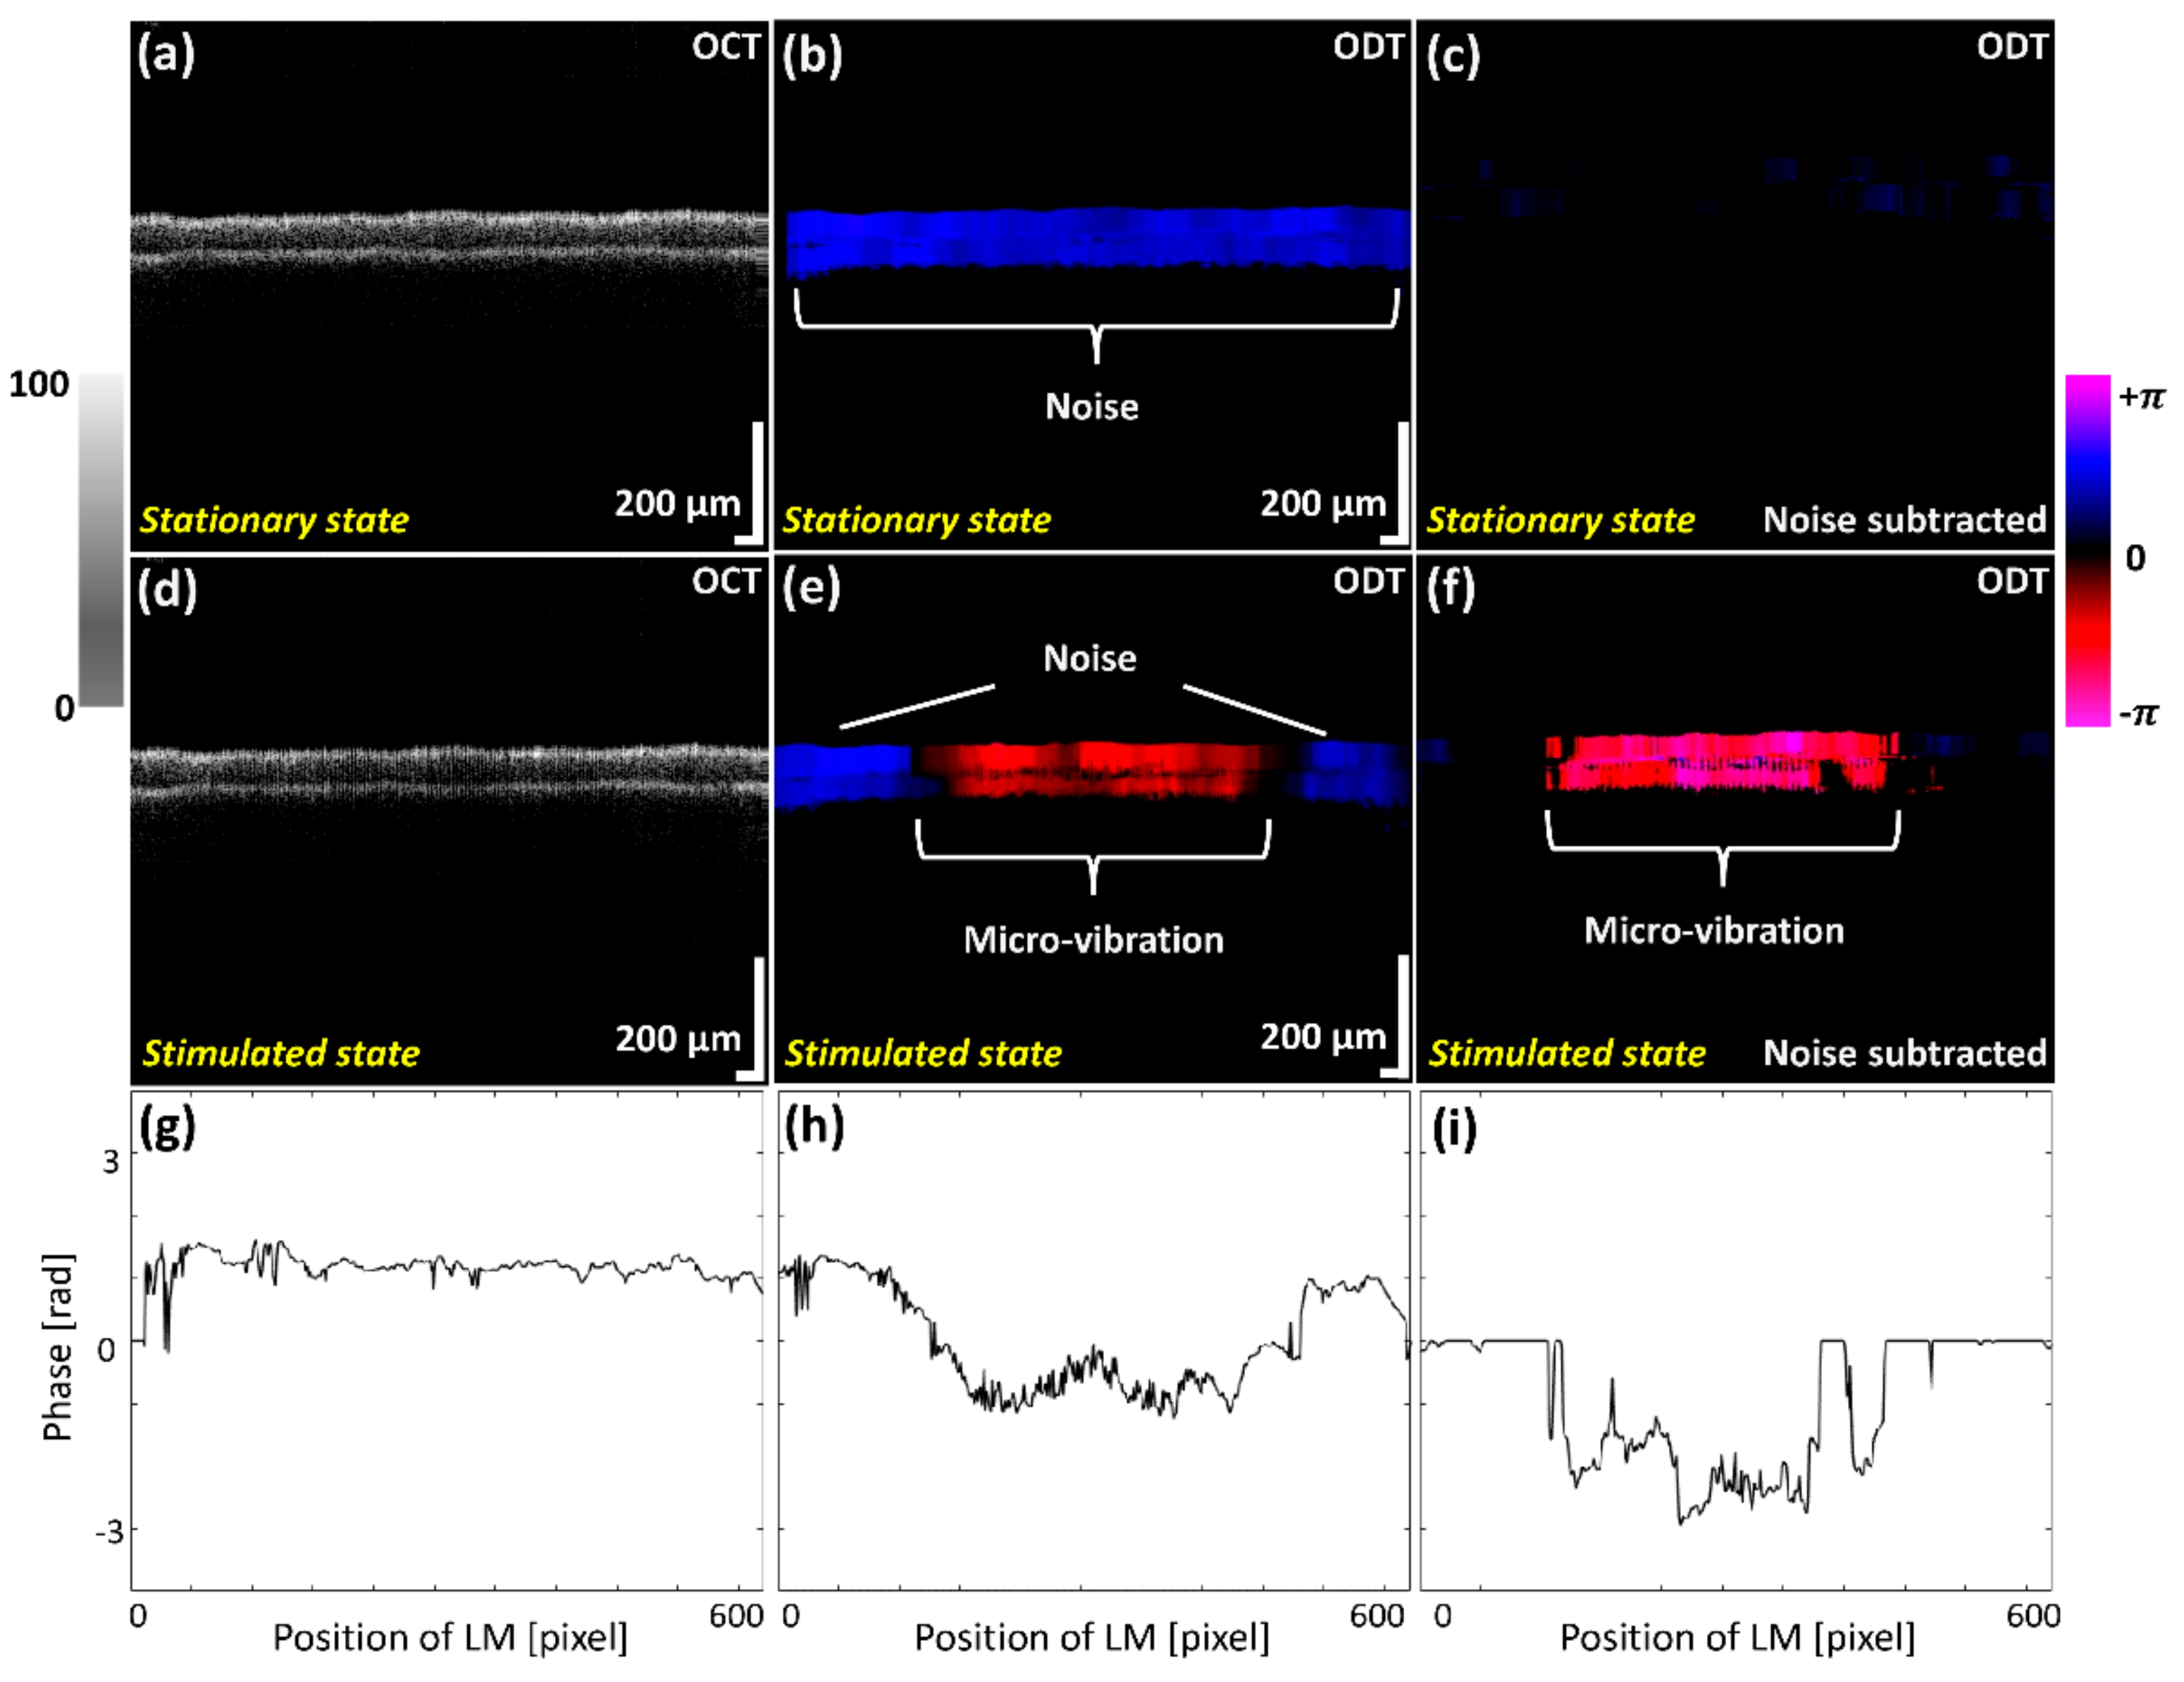

The micro-vibrations were investigated using OCT and ODT cross-sectional images while scanning the membrane before and after exposing to the diverse frequency ranges. Figure 4 shows the OCT and ODT results of the two different states before applying sound indicated as a stationary state, and after applying sound expressed as a stimulated state. The illustrated OCT and ODT results of Figure 4a,b were obtained during the absence of sound waves (control), where Figure 4d,e represent oscillation images of the latex membrane, which were acquired while providing a 2 kHz sound wave frequency. Although vibration effects can be slightly recognized in the grayscale OCT image of Figure 4d, identification of prominent fine oscillations is difficult to distinguish. Slightly occurred phase shift evaluations caused by micro-vibrations with external noise effect were color mapped in ODT results, as shown in Figure 4b,e.

Figure 4.

Two dimensional optical coherence tomography (2D-OCT) and Optical Doppler tomography (ODT) images acquired before and after exposing the latex membrane to the sound waves. (a) 2D-OCT image of latex membrane before applying sound. (d) 2D-OCT image of vibrating latex membrane. After Doppler image processing, (b,e) are 2D-ODT images with severe noise. (c,f) are processed 2D-ODT images with an algorithm to subtract phase differences before and after sound is applied, eliminating unnecessary noise at (b,e). (g–i) are indicated the phase data of (b), (e) and (f), respectively.

In order to eliminate the aforementioned noise effect, we used the phase subtraction method, comparing the phase difference before and after applying sound. The results of Figure 4c,f demonstrate the ODT images with the applied noise filtering software to minimize the unnecessary noise effect of Figure 4b,e. Although erroneous numerical values have been significantly reduced comparatively, slight noise signals were still left and unable to be removed in the (+) direction due to the sensitivity of measuring micro-vibrations and the inconsistency of phase shift generated by scanners. To quantitatively validate the effect of the phase subtraction method on the ODT image, the phase data of Figure 4b, e and f were plotted in Figure 4g–i. Figure 4g shows the initial noise generated from the external aforementioned factors. In addition, the result of removing a redundant noise, which is shown in Figure 4g, was verified by comparing with Figure 4h,i. After subtracting the noise, the pure fine vibration of the latex membrane was measured in this study. These results revealed that the noise removal was sufficiently accomplished to verify the micro-vibration of whole latex membrane.